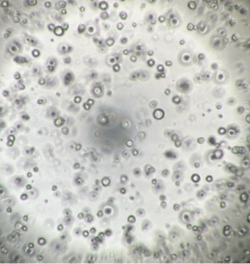

InnoCell(R)プレートシリーズは、体外での細胞培養において、各々の細胞に適した酸素供給を実現できます。その機能により、長期間、元気な細胞を体外で培養できるうえ、スフェロイドの内部で起こる壊死を軽減できるため、正確な医薬品のスクリーニング結果の提供に期待されています。また、これまで体外で培養が難しかった、ヒト膵がん患者由来オルガノイドの増殖性の向上により、個別化医療における患者さんに適した医薬品の早期提供の可能性も期待されています。

さらに、プレートへの薬剤の吸着性が低く、ガラスに匹敵する蛍光観察性能を備えています。試験に供した薬剤が正確に細胞へ作用し、細胞の構造、機能などが可視化できる価値も認められています。